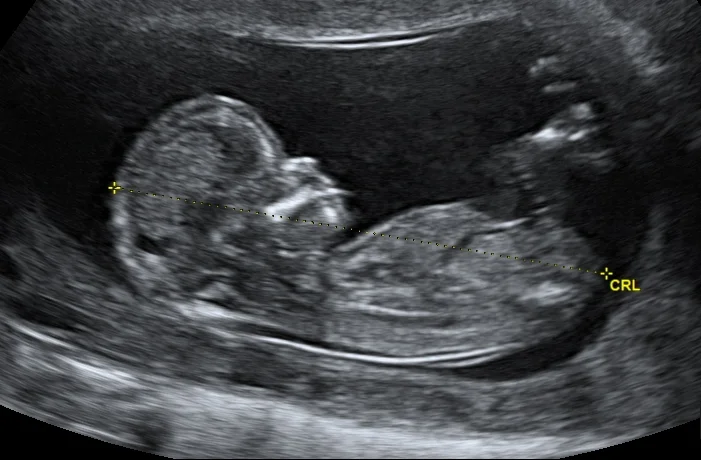

Read MoreResuscitative hysterotomy is the emergent delivery of a foetus from a mother in cardiac arrest to improve the outcomes of both the mother and foetus.